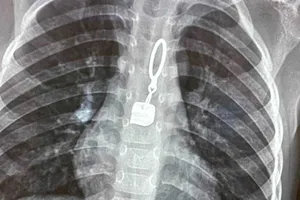

Gắp chiếc khoá áo kim loại mắc trong thực quản bệnh nhi 40 tháng tuổi Y tế - Sức khỏe 05/01/2023 10:57